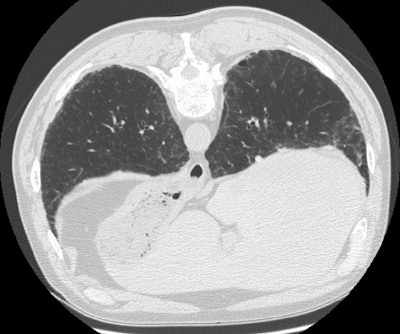

Asbestosis:

Patient with a history of asbestos exposure

Lung windows demonstrate inter and intralobular septal thickening and there is a curvilinear subpleural line seen in the lateral aspect of the right middle lobe.